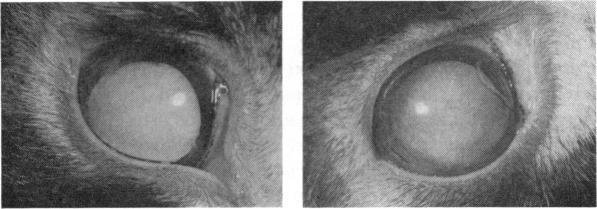

A Clinical and Experimental Study of Electric Cataract.

Trans Am Ophthalmol Soc. 1962;60:471-516.